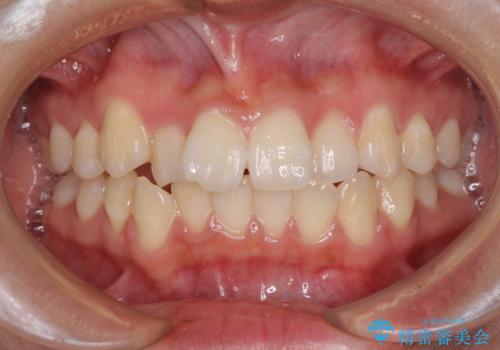

- 上下のデコボコと前歯のクロスバイトを改善したいとのことで来院された患者様です。

極力短期間で治療したいとのことで、ワイヤー装置による矯正治療を行うこととしました。